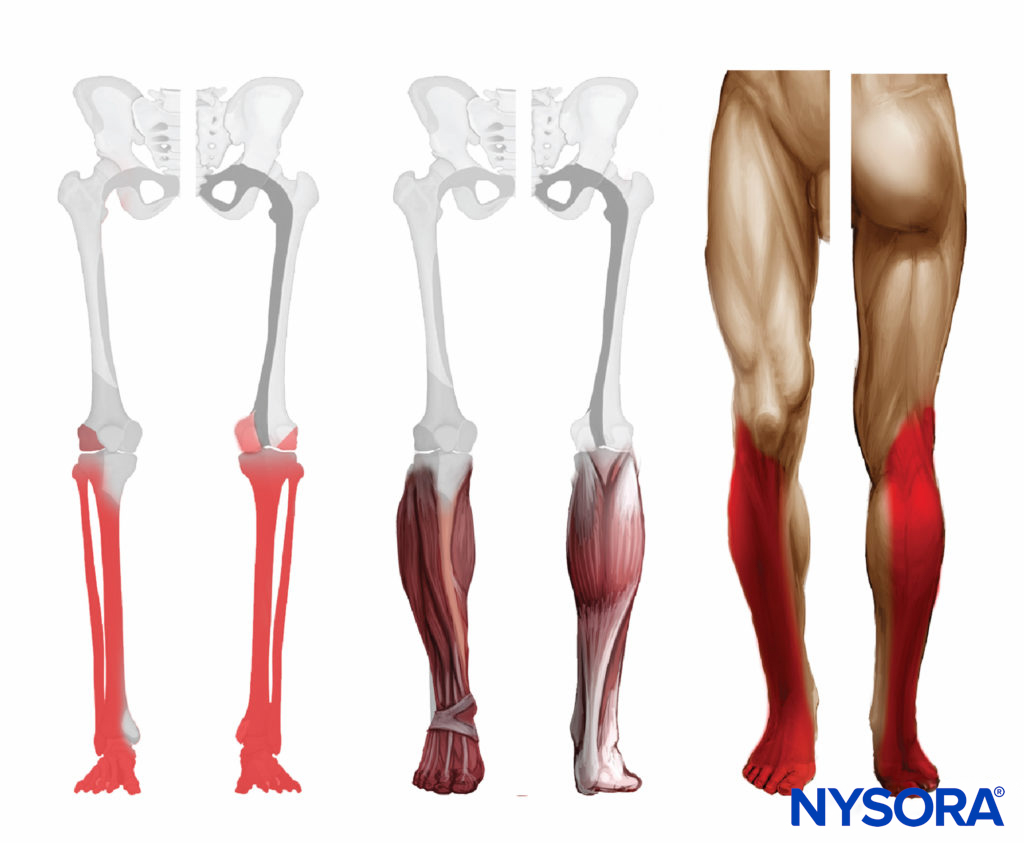

block DISTRIBUTION

Sciatic nerve block results in anesthesia of the lower limb below the knee, both motor and sensory, with the exception of the medial leg and foot, which is the territory of the saphenous nerve, a branch of the femoral nerve. The motor fibers to the hamstring muscles are spared; however, fibers to the posterior aspect of the knee joint are blocked (Figure 5).

FIGURE 5. Expected distribution of the sciatic nerve sensory block at the level of the popliteal fossa.